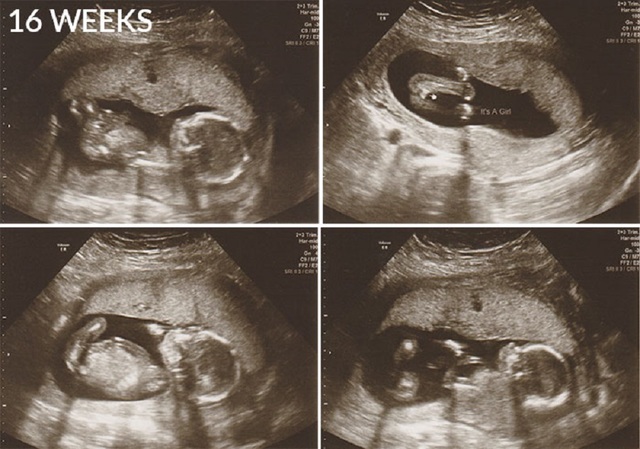

• Semana 15 y 16

Semana 15 y 16

Al finalizar el cuarto mes mide entre 15 y 20 cm y pesa de 120 a 200 gr, aparecen las cejas, pestañas y pelo en la cabeza (lanugo) que desaparecerá entre el octavo y noveno mes. El producto comienza a mover sus articulaciones.

La piel es transparentes, los huesos y tejido muscular continúan desarrollándose y los huesos se hacen más duros.